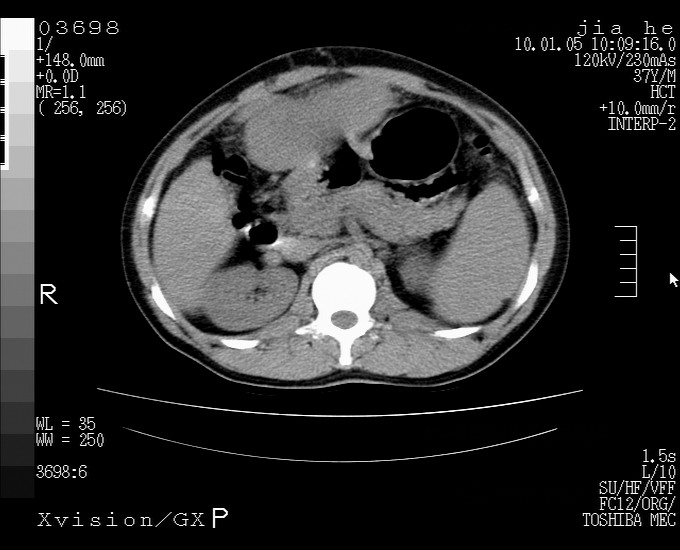

标题: CT23988:男,40岁,B超提示腹部肿物,请各位老师给看看。 [打印本页]

标题: CT23988:男,40岁,B超提示腹部肿物,请各位老师给看看。

左叶够大的,且与胰腺欠清晰,请增强扫描

考虑肝癌 请强化

肝癌并腹膜后淋巴西结转移

1.该患者有腹部手术史

2.脾大,肠系膜密度增高,有多发索条影,胰腺边缘毛糙,腹膜增厚,推测有肝硬化,门脉高压,腹膜炎和/或胰腺炎

3.肝左叶巨大站位,并腹腔淋巴结肿大,肝癌或肝间叶来源恶性肿瘤,也不排除大网膜间质瘤侵及肝左叶

建议:增强或磁共振

肝癌并腹膜后淋巴结转移

外生性肝癌并腹膜后淋巴西结转移!

考虑肝左叶外侧段癌并腹膜后淋巴结转移.建议增强进一步检查.